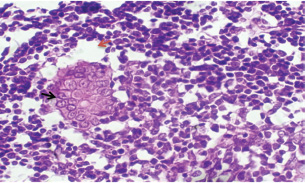

Theileri annulata appeared in various shapes, such as commas, dots, or rods, in addition to the deformation of red blood cells resulting from the effects of piroplasms or other shapes (Fig. 1).

Fig. 1. T. annulata inside erythrocytes (black arrow) in thin blood smears of infected rabbit stained by Giemsa stain (100×).